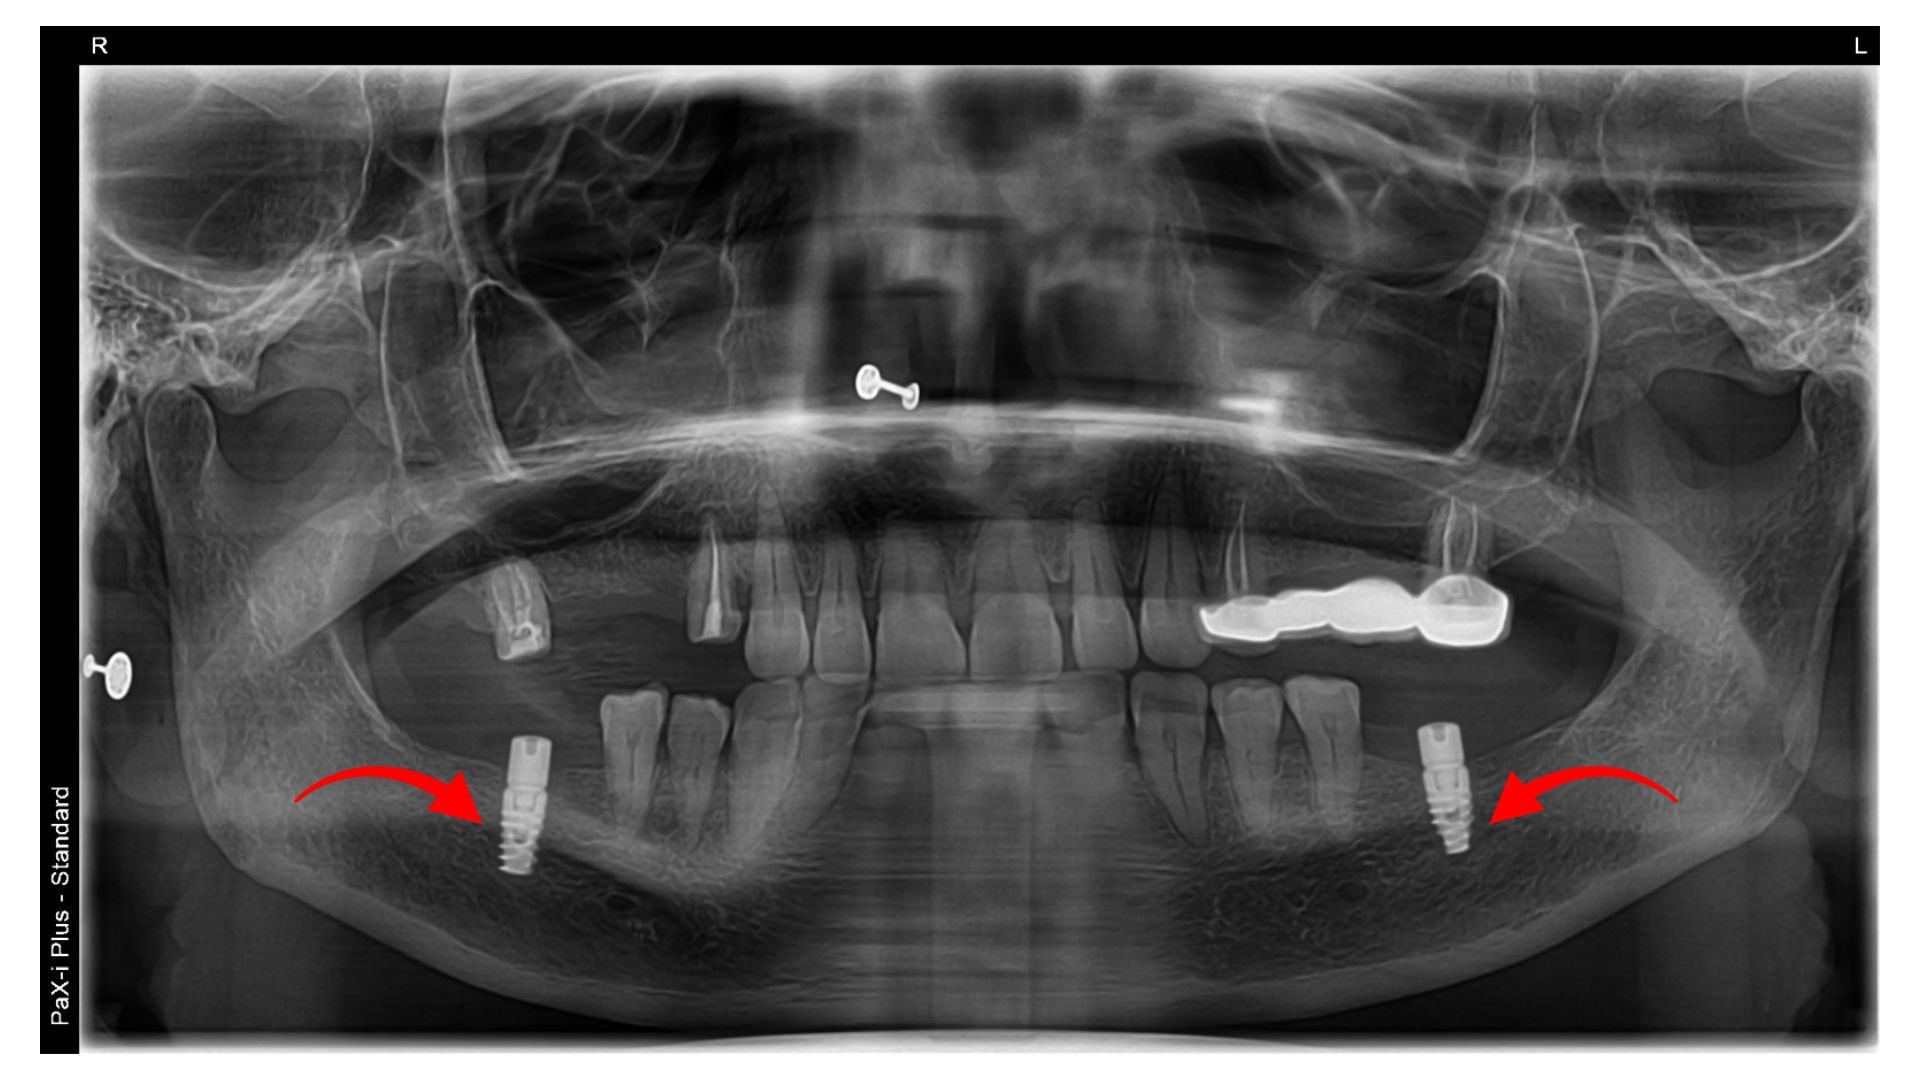

Full arch implants are used for replacing all the teeth of the jaw or to rehabilitate a completely edentulous jaw. All-on-4 treatments include using 4 implants to replace all the teeth of the arch, while all-on-X treatments include 4-8 implants in one arch. These treatment protocols offer a fixed and stable solution for patients with no teeth.

Implants are a surgical treatment, and the entire workflow from the placement of the implant screw to the final prosthesis works on the same principles, regardless of the type of the implant. Here we have discussed the procedure for endosteal implant placements, as followed at our practices in Hyderabad, India

A comprehensive oral examination is performed, followed by X-rays or a CBCT scan. Bone density and gum health are evaluated. The situation and suitable treatment options are explained to the patients

Patient scans are used to choose the implant size; the requirement of bone grafting or other procedures is identified. The timeline, costs, and procedural steps are explained to the patient, and an implant surgery date is fixed according to patient comfort.

Implant surgery involves placement of the titanium implant screw into the jawbone; this is performed under local anesthesia. The implant is covered with a healing cap, and sutures are placed to protect the site of surgery.